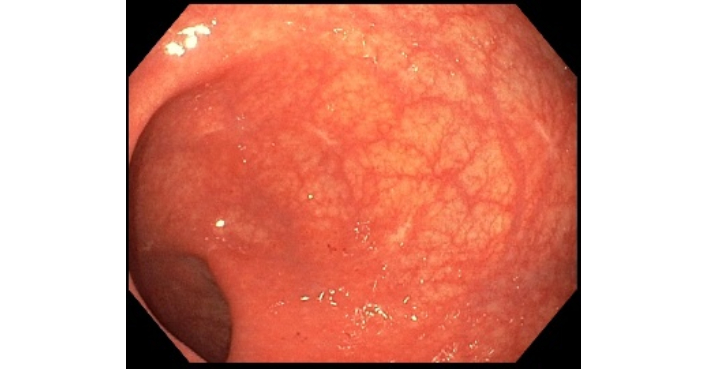

Approximately 4 months after discontinuing IXE and 3 months post-extended right hemicolectomy with end ileostomy, the patient underwent ileoscopy and flexible sigmoidoscopy with our team for disease surveillance. Ileoscopy revealed a normal-appearing ileum, with findings confirmed on histology (Figure 8). Flexible sigmoidoscopy showed normal descending and sigmoid colon and mild rectal changes, including faint erythema and punctate hemorrhages with air insufflation, endoscopically suggestive of mild diversion colitis (Figure 9). Sigmoid biopsies revealed focal active colitis without evidence of chronic changes, whereas rectal biopsies demonstrated mild chronic active colitis with non-necrotizing granulomata. Our team recommended a 3-month course of short-chain fatty acid enemas, followed by repeat flexible sigmoidoscopy and routine IBD surveillance labs to evaluate for resolution of mild colitis.

Flexible sigmoidoscopy findings. (A) Normal-appearing sigmoid colon. (B) Rectal changes are characterized by faint erythema and punctate hemorrhages caused by air insufflation.